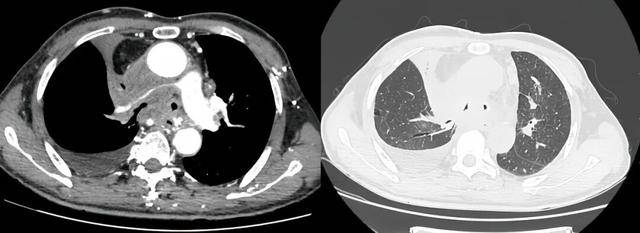

介入手术室里,一场无声的战役打响。麻醉科主任闫华凭借高超技术,成功为患者通气建立安全通路,为手术的实施奠定基石。介入科主任贺光辉带领团队细致操作,将一枚Y形气管支架在X线引导下输送至预定位置后精准释放,原本被肿瘤挤压得只剩一丝缝隙的气道被稳稳地撑开。紧接着一枚肺动脉覆膜支架置入到受压变窄的右肺动脉主干内并准确释放,再次造影,使得右肺动脉血流迅速得到改善。

手术过程